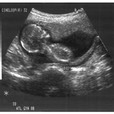

Because I spend half of my time teaching resident doctors and medical students, and the other half of my time taking care of patients in my Family Medicine office, some of the pages, such as “Childhood Vaccines” are designed for everyone. Other pages, such as US Videos, PE, and Procedure Videos are intended for Doctors and Students.